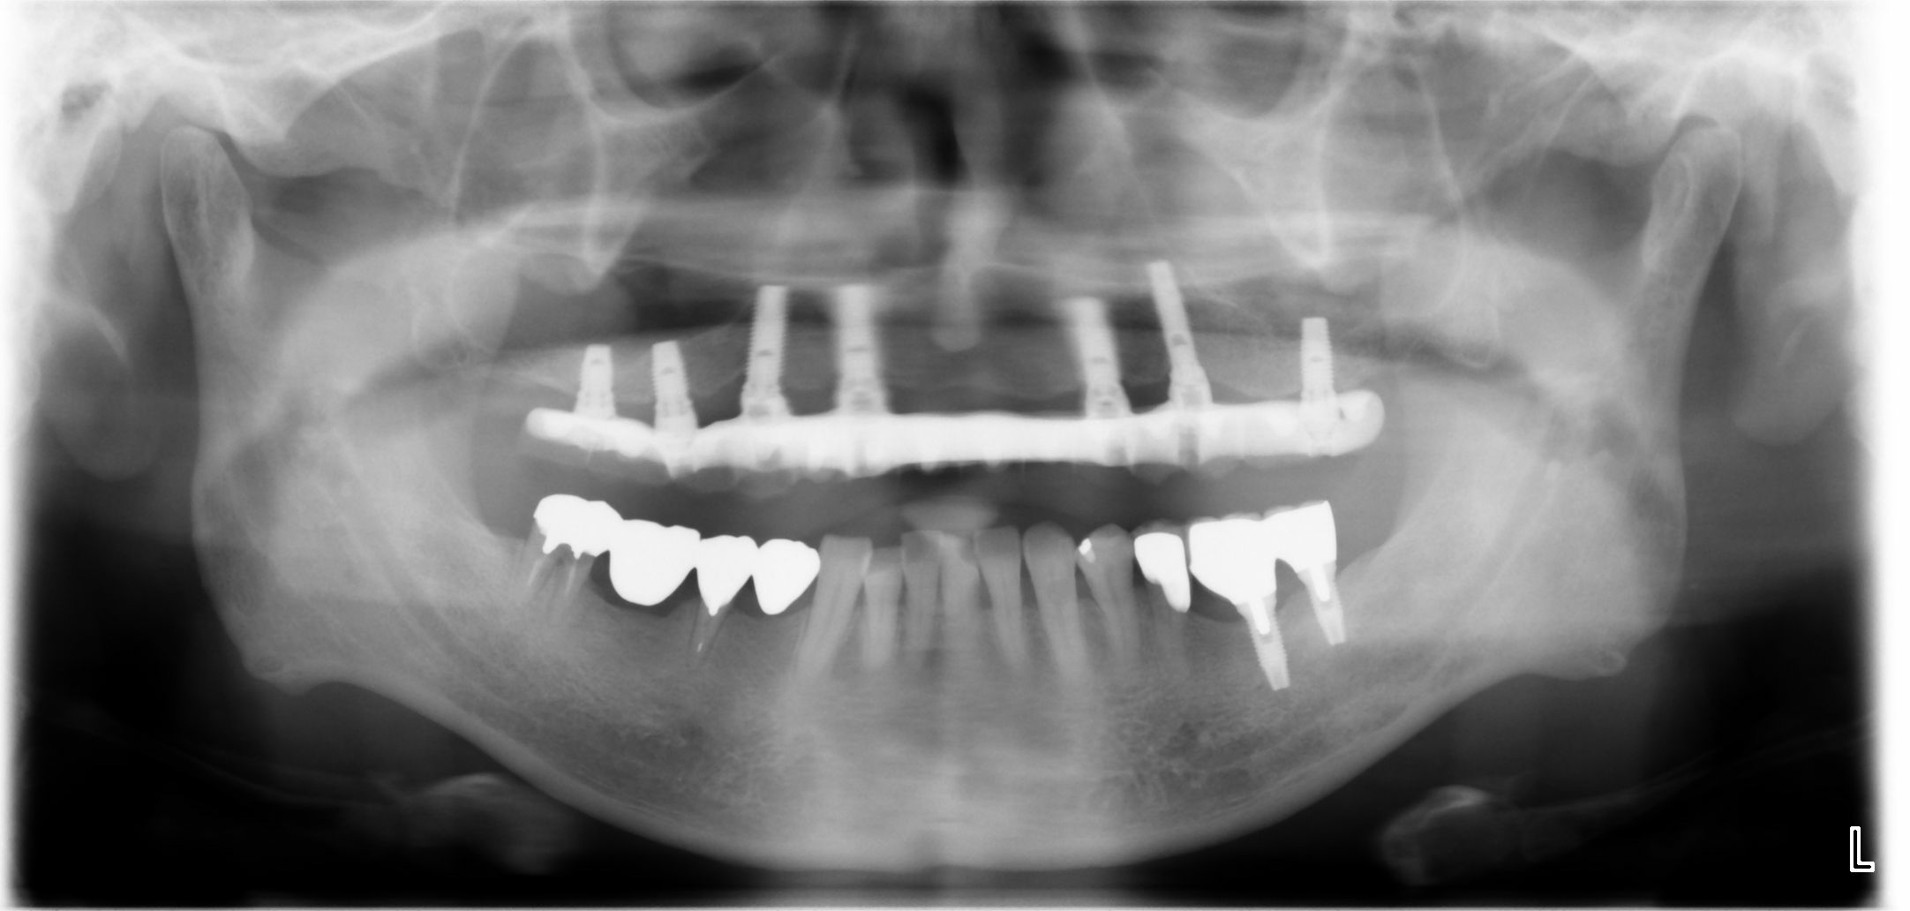

重度の歯周病により、他院で「総入れ歯にするしかない」と診断された40代の男性のケースです。

治療前(パノラマX線写真)

当院にて、歯周病治療で口腔内環境を整えた上でインプラント治療を行った結果、ご自身の歯のような見た目と噛み心地を回復。「人前で笑えるようになった」「食事が美味しい」と、健康な人と全く変わらない人生を取り戻されました。

治療後(パノラマX線写真)